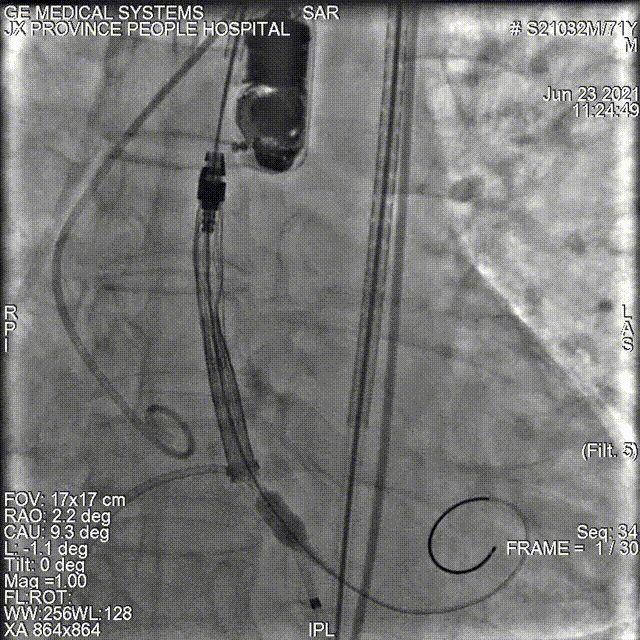

敖广球囊18mm预扩张

同时进行冠脉风险评估:观察球囊扩张对冠脉的影响